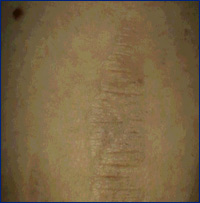

Outros usos incluem tratamento de estrias